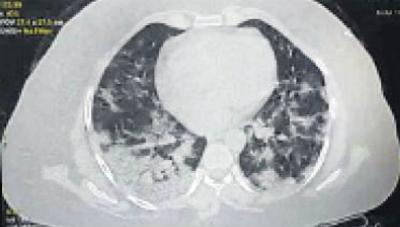

महिला १३ तारखेला उभीही राहू शकत नव्हती. तिला श्वास घेण्यास त्रास होता होता. ऑक्सीजन लेव्हल चेक केलं तर ९४ होतं. १३ तारखेला सिटी स्कॅन केला तर तिचे दोन्ही फुप्फुसांमध्ये ८० टक्के इन्फेक्शन झालेलं होतं.

हे बघून कोटाचे श्वास रोग तज्ज्ञ डॉक्टर के के डंग हे हैराण झाले. कारण केवळ २४ तासात तिची फुप्फुसे खराब झाली होती. त्यांनी इंदुरच्या एका डॉक्टरसोबत याबाबत चर्चा केली तर त्यांनी सांगितले की, हा नवा स्ट्रेन आहे ज्यामुळे असं झालंय.

डॉक्टरांनी सांगितले की, हा नवा स्ट्रेन वेगाने पसरत आहे. हा तरूणांमध्येही वेगाने लंग्स इन्फेक्शन पसरवत आहे. आपण या केसमधून शिकलं पाहिजे आणि लक्षणे दिसली तर टेस्ट केली पाहिजे. कारण कोरोना आता वेळ देत नाहीये. बीपी ऑक्सीजन लेव्हल, एक्स रे सगळं काही ठीक असल्यावरही एकदम लंग्स इन्फेक्शन होऊ शकतं.